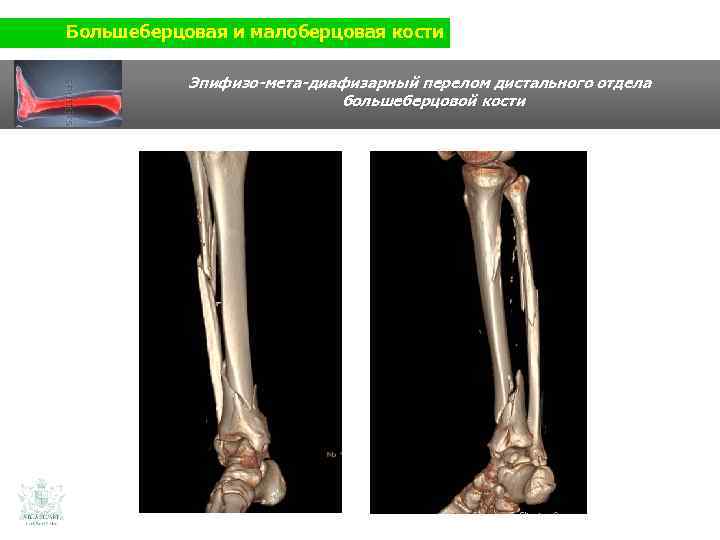

Большеберцовая и малоберцовая кости Клинический случай (большеберцовая и малоберцовая кости) Мужчина 60 ти лет Травма нижней конечности (авария на мотоцикле)

Большеберцовая и малоберцовая кости Эпифизо-мета-диафизарный перелом дистального отдела большеберцовой кости